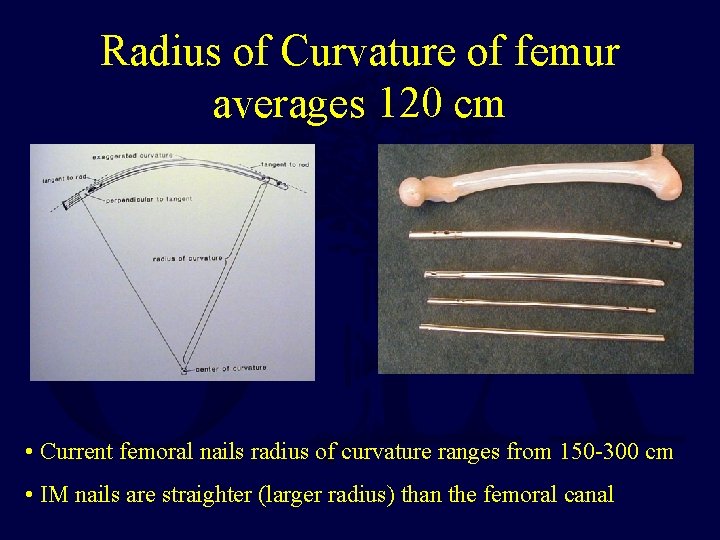

Radius of Curvature of femur averages 120 cm • Current femoral nails radius of curvature ranges from 150 -300 cm • IM nails are straighter (larger radius) than the femoral canal